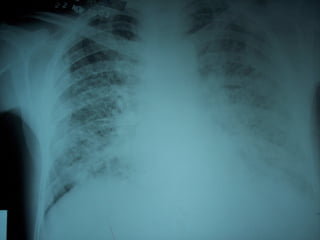

 Paciente varón que 52 años, diabético, que ingresa a la

emergencia por presentar tos, expectoración purulenta,

disnea, tirajes y fiebre.

 Es diagnosticado de sepsis pp pulmonar por una

Neumonía adquirida en la comunidad y DM

descompensada.

 A las 48 del ingreso el paciente evoluciona

desfavorablemente. Al examen se evidencia cianosis

perioral, confusión y una mala mecánica ventilatoria.

 Dada la presencia de signos de gravedad se decide su

pase a la UCI.

DIAGNÓSTICOS BRINDADOS POR

ELANALISIS DELAGA

 Insuficiencia respiratoria aguda tipo I.

 Gradiente A –a alto.

 Pa02/Fi02 en valores compatibles SDRA

moderado.

 Acidosis metabólica anión Gap alto, con

alcalosis respiratoria compensatoria y acidosis

metabólica anión Gap normal.

 Lacticidemía con hiperglicemia.